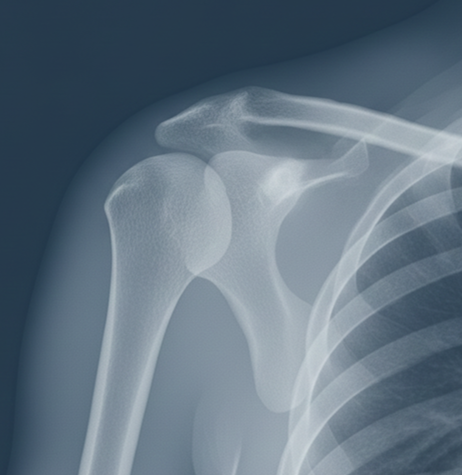

2. X-rays

Useful to identify:

- AC joint separation

- Early osteoarthritis

- Osteolysis

- Calcifications